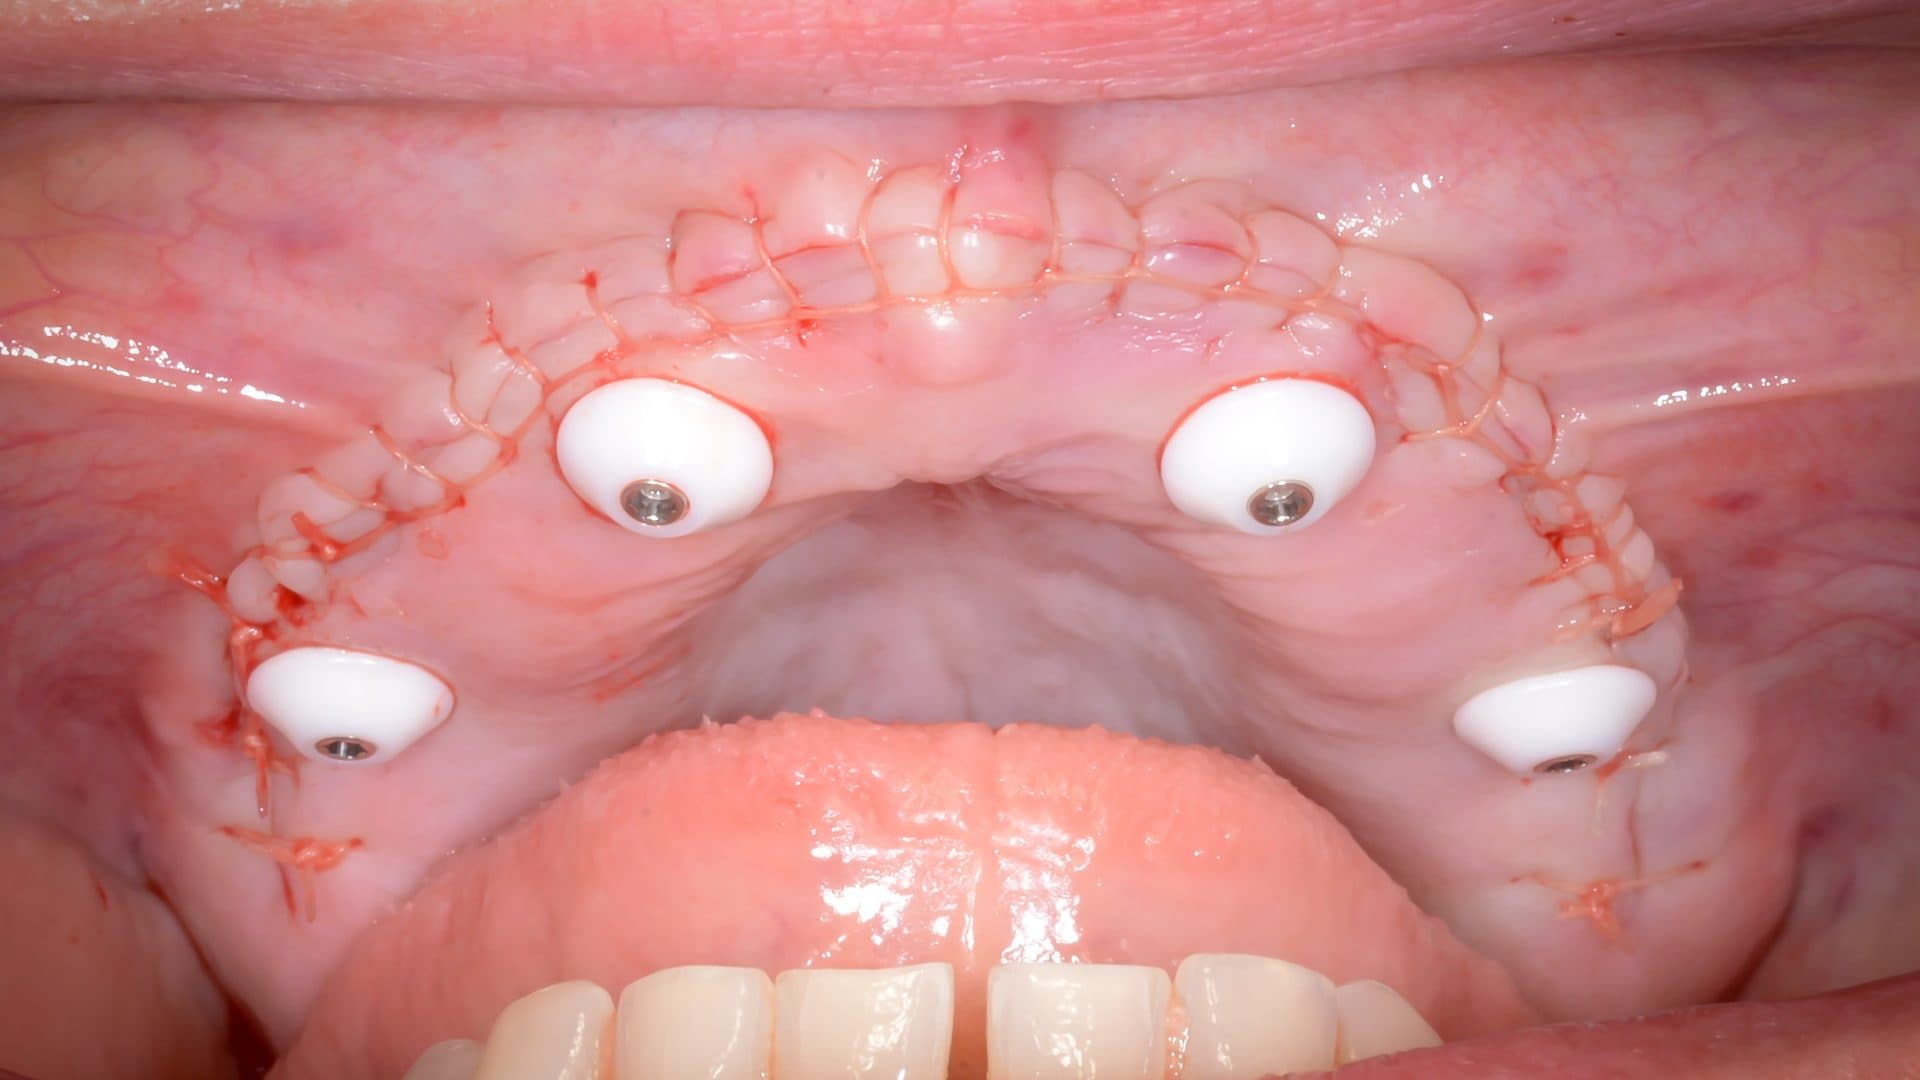

Here is a graphical overview of the ideal situation compared to poor standards with All-on-4 Plus® dental implants.

Ideal Situation

Poor Standards

As the surgery involves the jawbone, which is often already deficient, this treatment is difficult to undo and almost impossible to redo. This is surgery that also involves the mouth, which you use to talk, eat, taste, kiss, and smile, and when done incorrectly the treatment, being irreversible in its nature, could potentially commit a patient to a lifetime of new problems. Thus, as trusted clinicians we must always aim to get it right in the first place, but how can the patient know whom to trust?